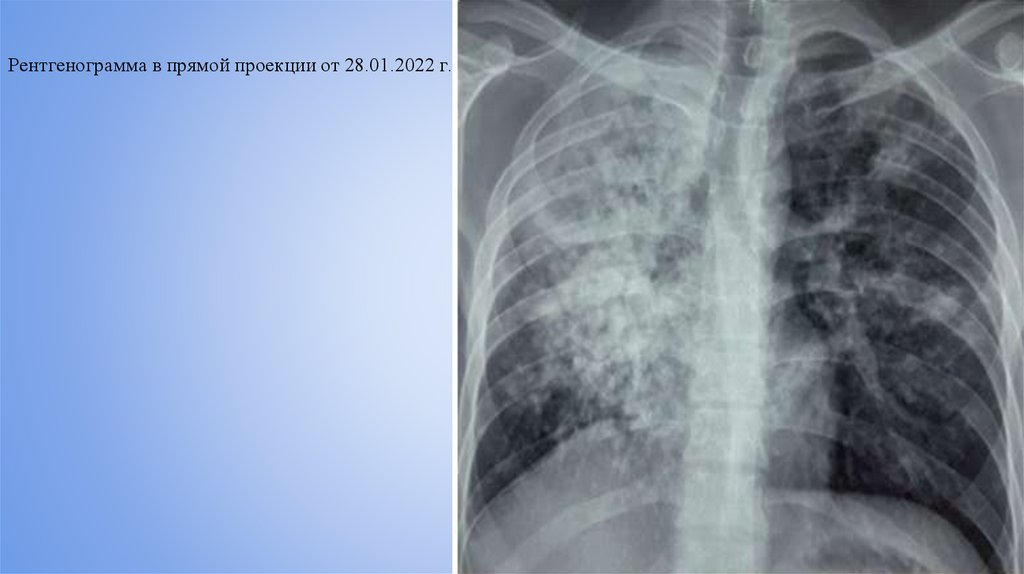

Рентгенограмма в прямой проекции от 28.01.2022 г.

Пациент Е., 31 год, 29.01.2022г. по 10.05.2022 г. находился на стационарном лечении в ЛТО-3 с

клиническим диагнозом: Инфильтративный туберкулез легких в фазе распада и обсеменения МБТ (+). НС.

ЛЧ форма. Сахарный диабет 2 типа, тяжелое течение, ИПП декомпенсация обменных процессов. Находился

в отделении 101 койко-день. Жалобы при поступлении: на кашель со слизистой мокротой, одышку,

потливость, общую слабость, быструю утомляемость, потерю в весе 20 кг. Анамнез болезни: ранее

туберкулезом легких не болел. Тубконтакт отрицает. Данное ухудшение состояния отмечает в течение

последних 2 месяцев. Начал терять в весе, появились кашель и рвота с кровью, повысилась температура тела

до 37,5 С. Обратился к терапевту по месту жительства. Проведена ЭФГДС. Заключение: эрозивный гастрит.

28.01.2021 г. бригадой скорой помощи доставлен в ГКБ №7. При дообследовании на КТ ОГК впервые

выявлены изменения, характерные для инфильтративного туберкулеза легких с распадом. Анализ мокроты

от 28.01.2022 г. на МБТ 2+, GeneXpert ТБ+, Rif чувствительный. Госпитализирован в ЛТО-3 ННЦФ РК.

В результате проведенного лечения у пациента наблюдалась положительная клинико-рентгенологическая

динамика. Жалоб нет. Устранены симптомы интоксикации, нормализовалась температура, прибавил весе 5

кг. В легких дыхание везикулярное, хрипов нет. Уровень глюкозы в крови нормализовался.

Рентгенологически в динамике - рассасывание инфильтрации и уплотнение очагов. Выписывается в

удовлетворительном состоянии для продолжения лечения по месту жительства